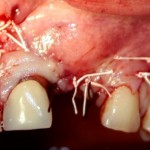

Трансплантация десны, аугментация лунки

Для определения размеров будущего мягкотканного аутотрансплантата мы использовали пародонтологический зонд. С помощью него мы выбрали донорскую зону (бугор верхней челюсти или небная сторона альвеолярного отростка верхней челюсти в области моляров), с помощью скальпеля получили необходимый по размеру аутотрансплантат (мягкотканный лоскут для пересадки).

Затем, мы подготовили ксенографт Bio-Oss Collagen. Обычно на 2 зуба (центральных резца) с избытком хватает 100-миллиграмовой упаковки. Имеющийся в ней параллелепипед мы поделили на 2 усеченные пирамиды с основанием в 2/3 ширины изначального блока.

Если вы когда-нибудь видели подобные операции, то наверняка обращали внимание на порядок действий — сначала устанавливаются имплантаты, затем укладывается графт и только потом фиксируется мягкотканный аутотрансплантат. Для удобства в этом и похожих клинических ситуациях мы поменяли порядок действий:

Сначала мы провели и зафиксировали деэпителизированный соединительнотканный аутотрансплантат (ССТ). Для этого мы сформировали тоннель и использовали ортодонтическую проволоку в качестве проводника. Подробнее об этой методике можно почитать здесь>>.

Затем уложили ксенографт. Особенностями Bio-Oss Collagen являются удобство адаптации, устойчивость к вымыванию и выдавливанию, поэтому мы просто уложили полученные ранее пирамидки вестибулярно относительно будущего имплантата, после чего прижали их с помощью уже упоминавшихся аналогов имплантата, входящих в хирургический набор имплантационной системы Xive (кстати, при работе с другими имплантационными системами для паковки графта в лунке можно использовать круглые остеотомы для синуслифтинга).

В совокупности, аугментация лунок перед установкой имплантатов занимает около 20 минут — и это самый долгий из всех хирургических этапов лечения.